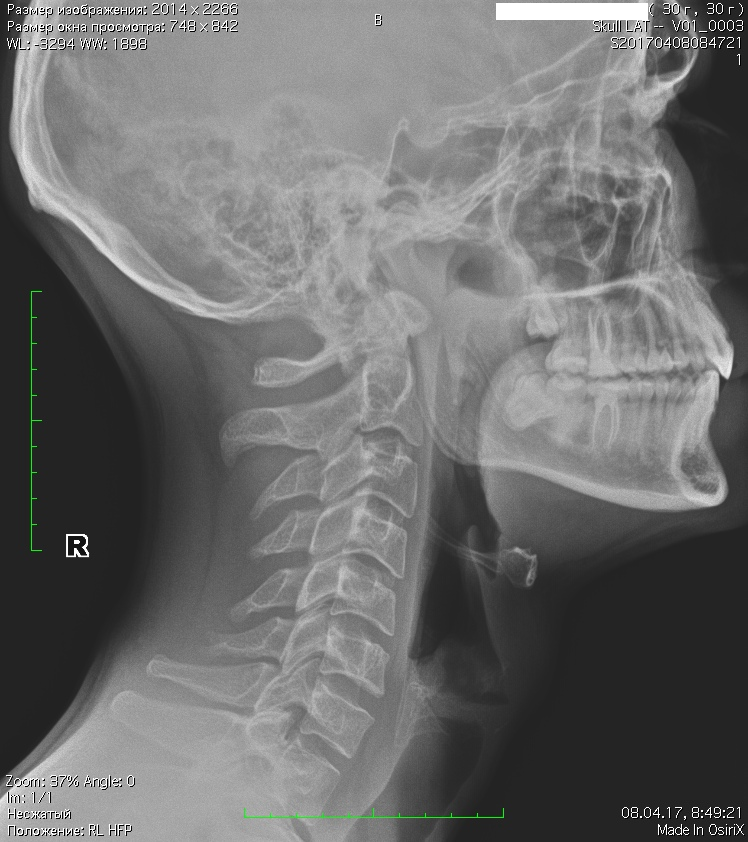

Рентгеновские снимки головы кошки в боковой проекции